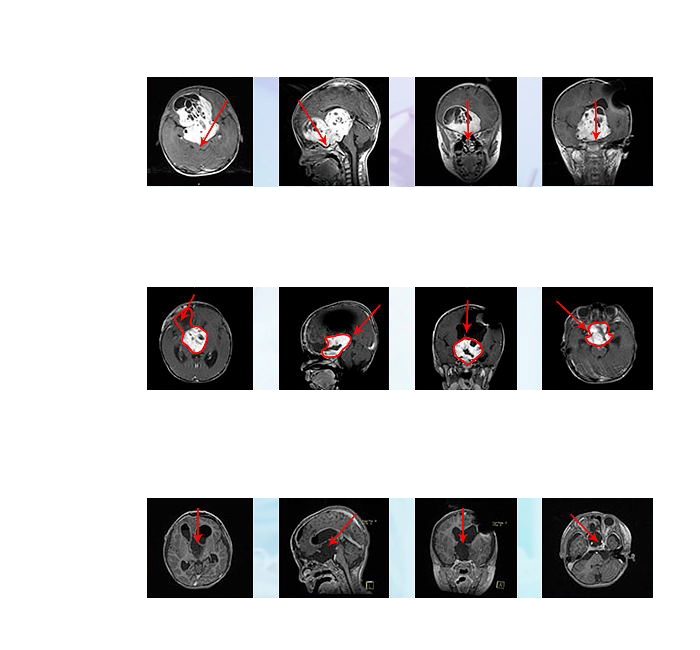

后小冬一家人通过INC咨询到德国INI国际神经学研究中心手术,主刀医生是INC国际神经外科顾问团(WANG)之国际颅底肿瘤手术教授德国Helmut Bertalanffy(巴特朗菲)教授,并由INC国际儿童神经外科教授、德国INI小儿神经外科主席Concezio Di Rocco教授联合为其提供完善的治疗方案。在德国INI的二次手术,从术前侵袭至双侧额叶及三脑室的较大瘤体,到术后影像上未见瘤体,从几近失明到逐渐地视力恢复接近正常,小冬的手术效果可以说是教科书级的示范案例。